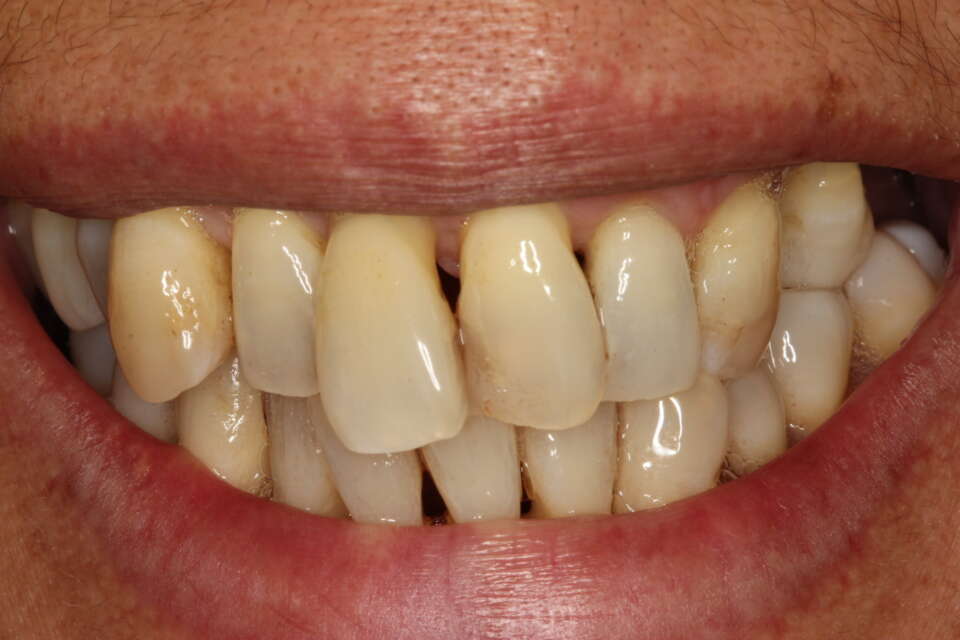

Before Treatment

IMG 6763

It is never too late to enhance your smile with our patient being in the last 60's. Quite severe crowding present but she only wanted to treat her front teeth.